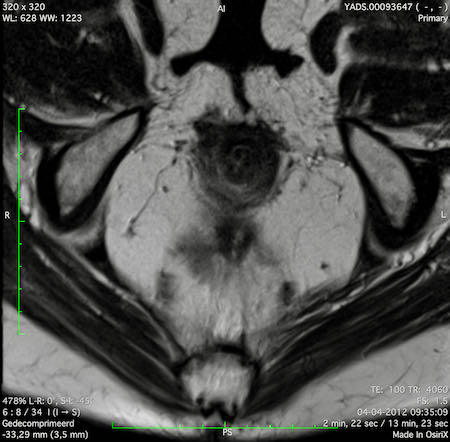

Đặc điểm MRI

- Thường khó xác định

- Thường biểu hiện nhưdày thành ruột lan tỏa, đoạn dài

- Kiểu tăng trưởng dưới niêm mạc, cho ra mộtHình ảnh “bia” (target)trên các hình ảnh cắt ngang

- Thâm nhiễm mỡ trực tràng lan tỏalà phổ biến

Hình ảnh

Các hình ảnh được cung cấp cho thấy ung thư biểu mô tế bào nhẫn với tình trạng dày lan tỏa thành trực tràng, hình ảnh bia bắn điển hình, và sự xâm lấn mỡ mạc treo trực tràng.